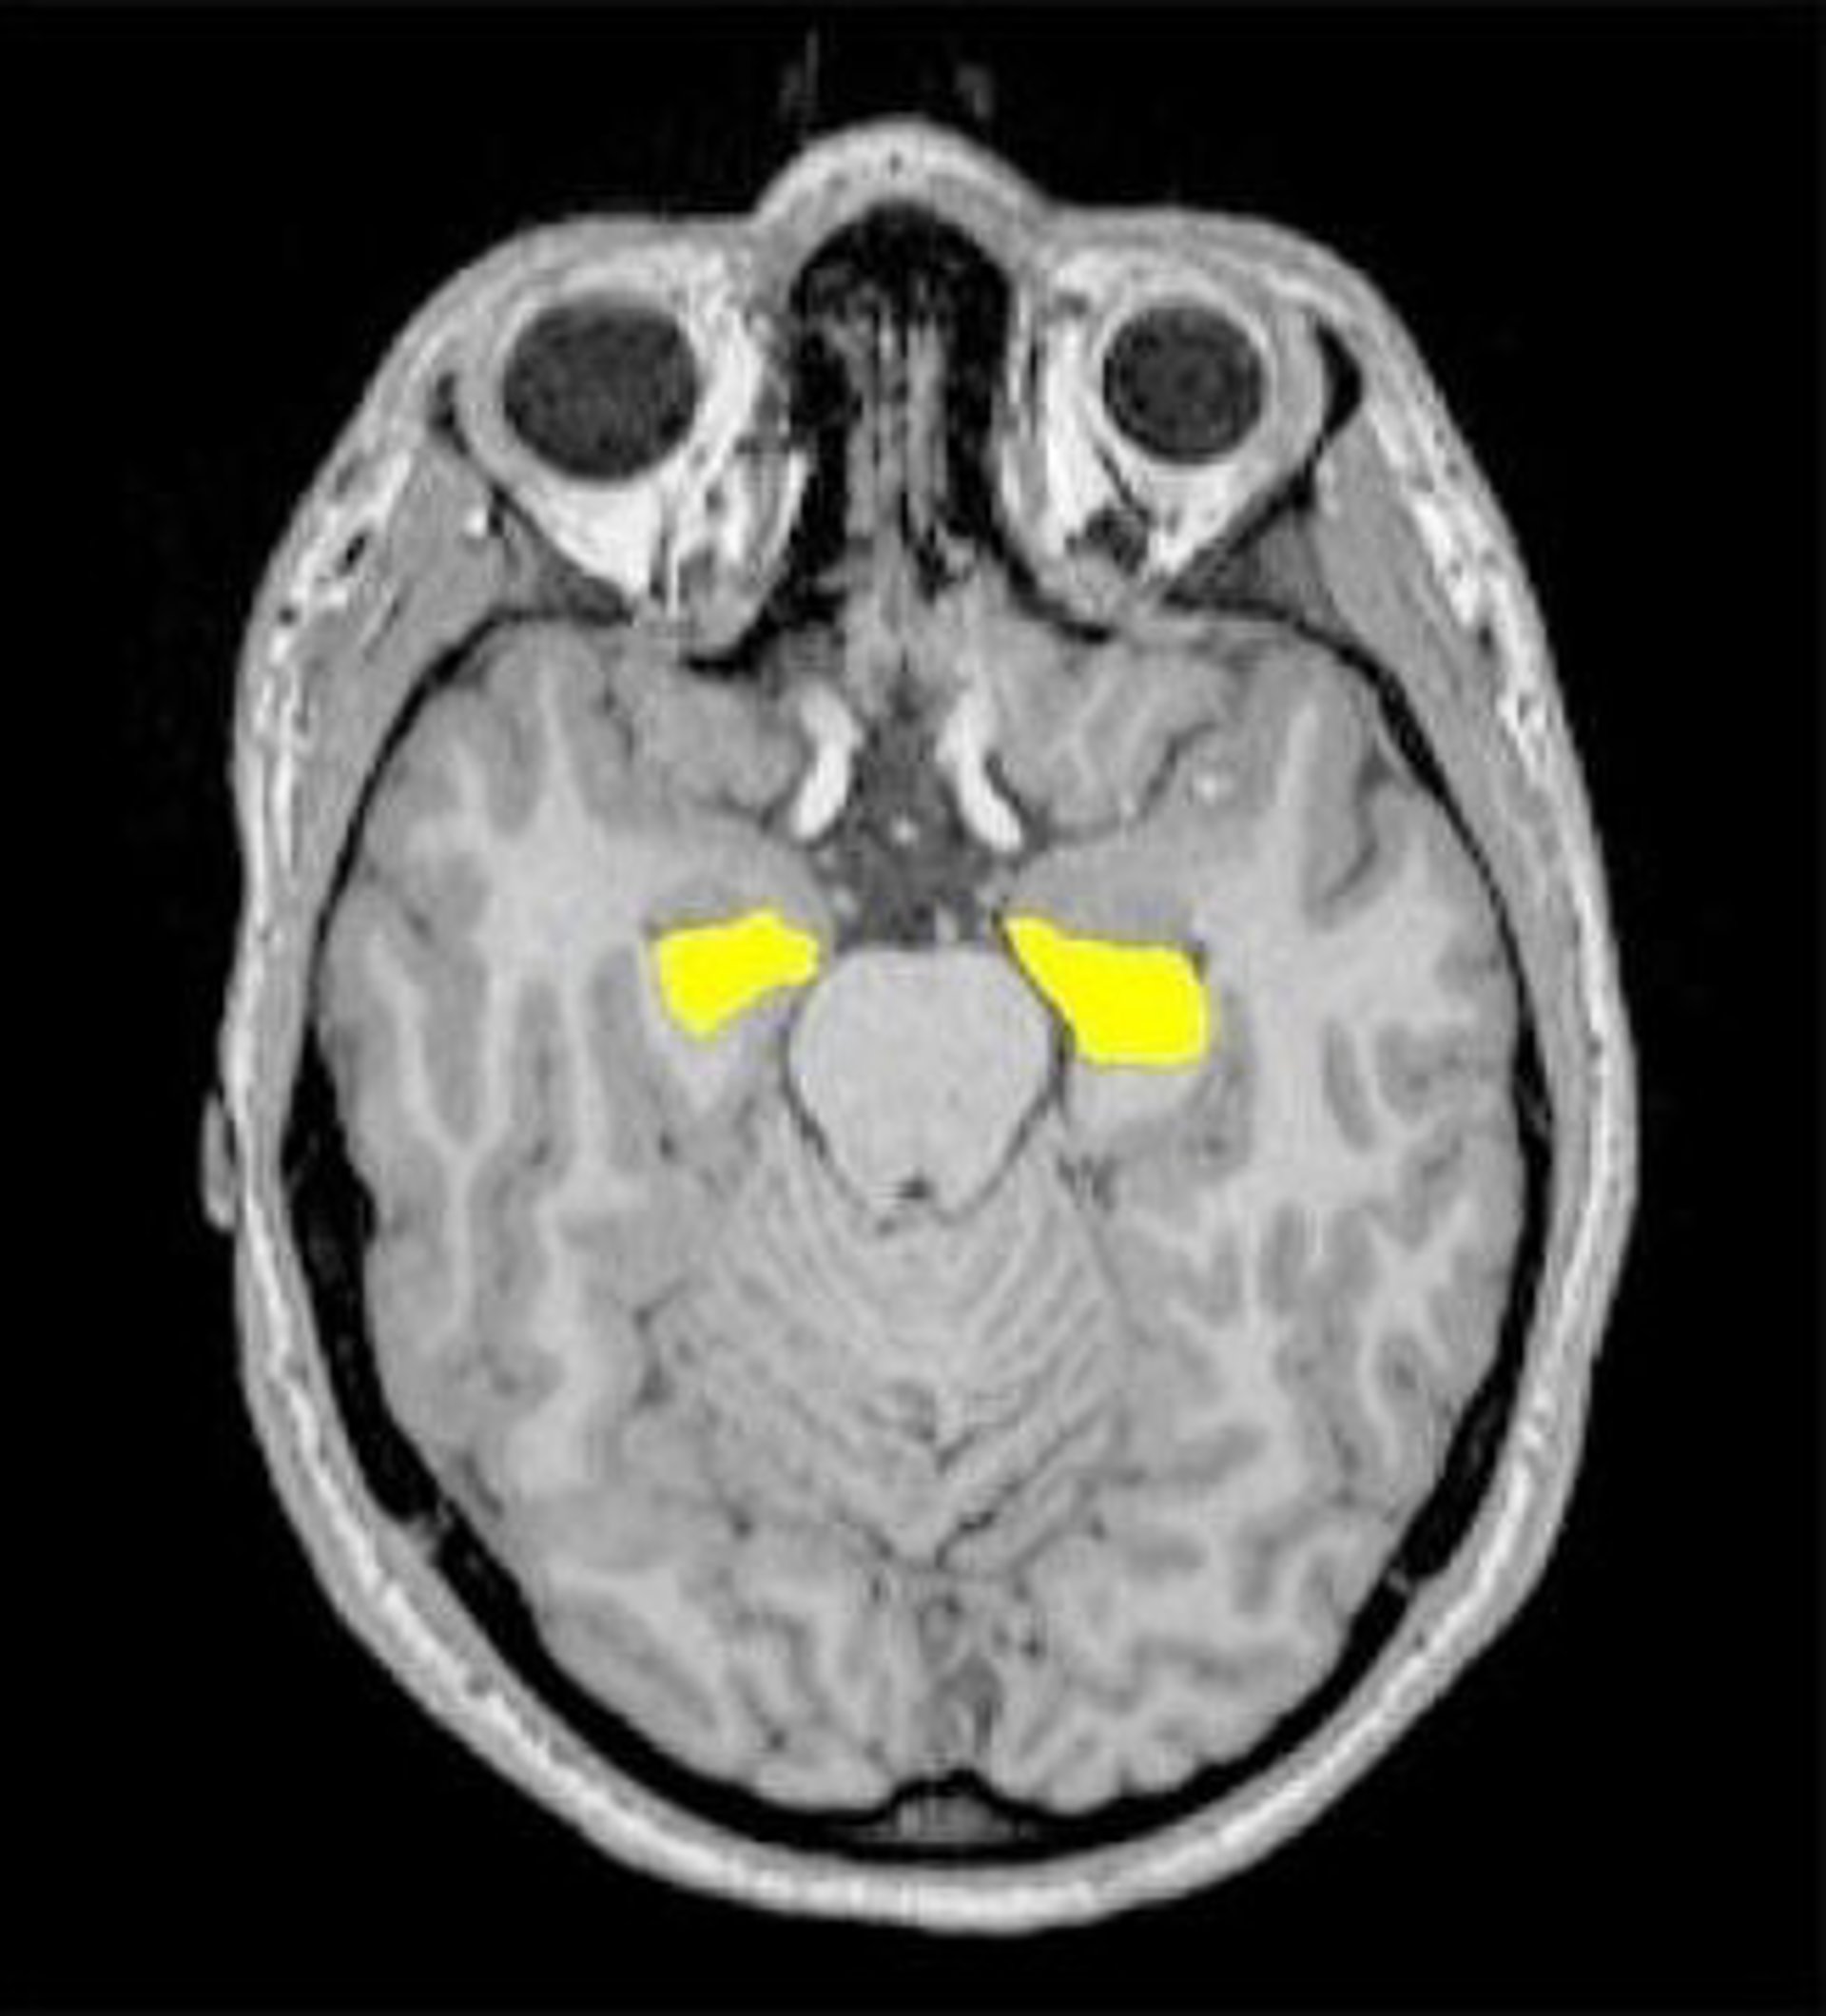

Descubren la relación entre los genes de la esquizofrenia y el tamaño del hipocampo

Hipocampo

NEUROPSYCHIARTY AND BRAIN IMAGING GROUP, BASEL

Cuanto mayor es el número de genes de riesgo en una persona con trastornos psiquiátricos menor es el volumen de su hipocampo en el lóbulo temporal, según un estudio realizado por los científicos de la Universidad de Basilea, Fabienne Harrisberger y Stefan Borgwardt, junto a investigadores de Transfaculty Research Platform.

La psicosis esquizofrénica es un trastorno psiquiátrico originado por una combinación de factores biológicos, sociales y medioambientales, que se relacionan con cambios en la estructura del cerebro. En este sentido, el análisis ha revelado que el grupo de genes de riesgo está conectado con una reducción en el tamaño de la región crítica del cerebro antes de la aparición de los primeros síntomas de la enfermedad.